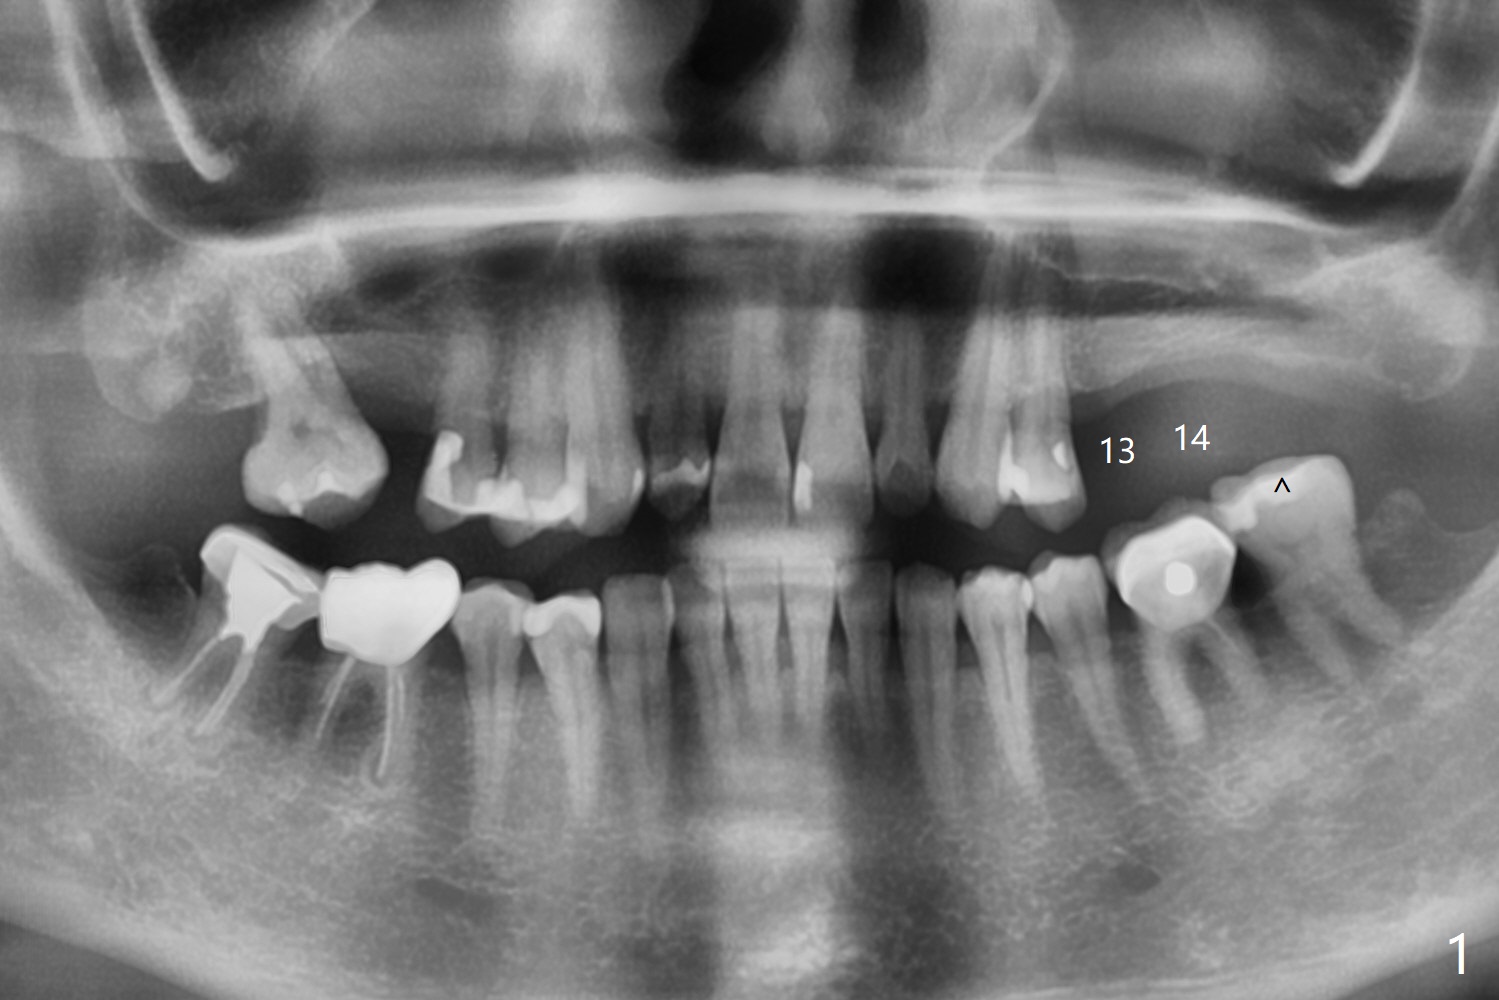

A 55-year-old woman agrees to have implants at #13 and 14 (Fig.1). There is no vertical space for implant at #15 because of supraeruption of #18 (^). A short FC implant will be placed at #13 without sinus lift (Fig.2), while sinus lift is required at #14 (Fig.3) using sinus lift drill or Magic sinus lifter. Prepare PRFx2 and small amount of sticky bone to cover #14 implant. Use acrylic to cover the bone graft. The acrylic will be retained by #13 abutment.